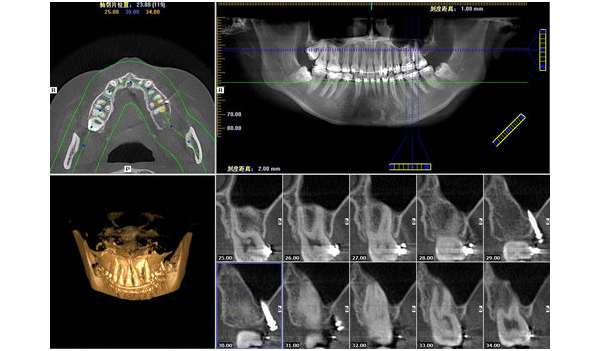

口腔种植科是_先应用CBCT并且是应用_多的口腔临床科室之一。CBCT能为口腔种植提供精确的三维影像,可以很好的显示颌骨的骨质、骨量及下颌神经管、上颌窦等组织结构。当前CBCT结合第三方软件Simplant进行种植手术,CBCT扫描后数据输入Simplant后进行模拟种植,建立可视化三维模型,并在其上设计_佳手术方案,制作种植手术导板,将种植体的理想位置转移至患者颌骨内,大大降低了种植手术风险。

随着CBCT的发展和在临床上的应用,为牙体牙髓疾病的诊断和治疗提供越来越多的帮助。CBCT能清晰、立体的在颊舌向、水平位和轴位上显示上下颌牙齿根管数目,根管的走形。如在临床中,牙体牙髓科医生首选根尖X线片,但对于根管结构复杂,如上颌磨牙的近中颊侧根第二根管,根尖片正常角度投照,二维影像叠加,第二根管影像难以显示,这就需CBCT扫描重建获得轴位、颊舌向影像,以清晰显示根管数目、走形以及根管口的位置,为根管治疗提供有力帮助。另外CBCT对于牙齿骨折尤其是牙根纵裂有较高的诊断准确率,牙根纵裂通常是面向颊舌向的,如果X射线束没有沿纵裂线直接通过,则根尖片没有明显表

现,而CBCT能准确的发现牙根纵裂等。